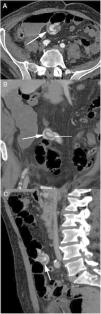

The presence of an MD in a MDCT should be suspected when a blind tubular structure connected to the terminal ileum by a neck of variable size is observed. Multiplanar 2D reconstructions images and CT enterography can help in the diagnosis. In patients with symptoms of obstruction or intestinal inflammation, the possibility of a complication secondary to a MD should be considered, especially when the terminal ileum and the vermiform appendix are normal. MDCT angiography, in cases of acute gastrointestinal bleeding, can identify contrast extravasation and accumulation of blood in the MD, and could demonstrate the persistent omphalomesenteric artery, which is diagnostic of MD. Other MDCT findings such as the presence of enteroliths or associated inflammatory changes around the MD can facilitate the preoperative diagnosis of MD complications.